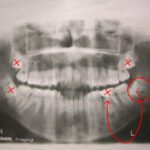

Η οδοντοφατνιακή χειρουργική, ή όπως πολύ συχνά αναφέρεται και στοματική χειρουργική περιλαμβάνει και την εμφυτευματολογία,  την αφαίρεση εγκλείστων δοντιών (κυρίως των φρονιμιτών), αφαίρεση μικρών κύστεων, αποκάλυψη εγκλείστων δοντιών, σύγκλιση στοματορινικών συριγγίων, κ.α.

Τέλος οι γνωστοί σε όλους μας φρονιμίτες που δημιουργούν πολλά και έντονα προβλήματα, κυρίως σε νεαρή ηλικία και όχι μόνο.

Μία συχνή επέμβαση που πολλοί τη θεωρούν σχετικά απλή, αλλά στην πραγματικότητα πολλές φορές δεν είναι έτσι.